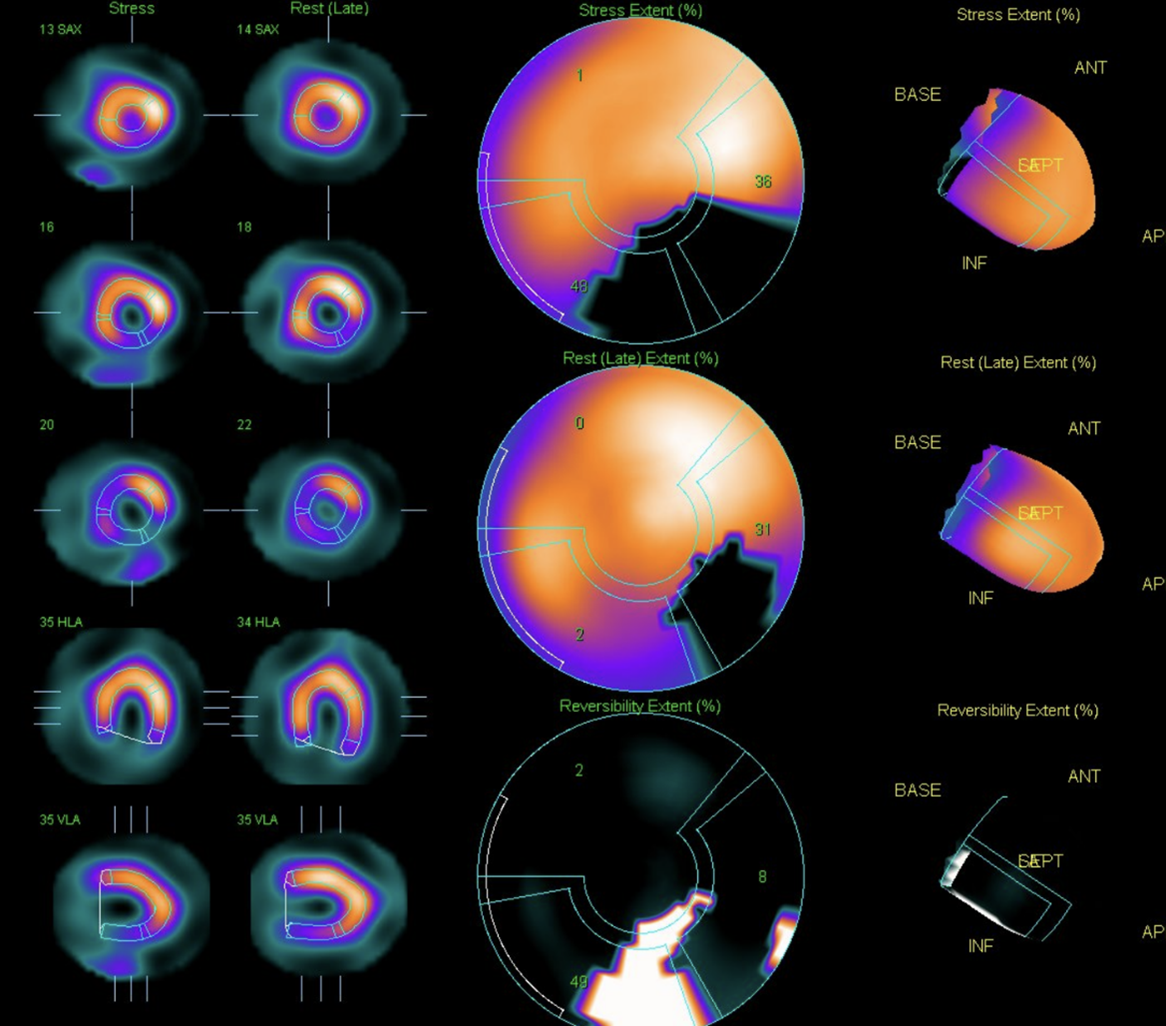

The laboratory test showed white blood cell count (WBC) of 7.8x10^3/uL, hemoglobin (Hb) level of 15.1gm/dl, platelet count of 181x10^3/uL.The glucose level is 98mg/dL, The liver enzyme levels show GOT (AST) at 19 U/L and GPT (ALT) at 22 U/L. Lipid panel results include HDL-C at 44mg/dL, LDL-C at 62mg/dL, triglycerides at 101mg/dL.Creatinine level of 0.75 mg/dL (eGFR:108.53) Tl-201 myocardial perfusion scan showed abnormal uptake in inferior, inferolateral, and septal wall